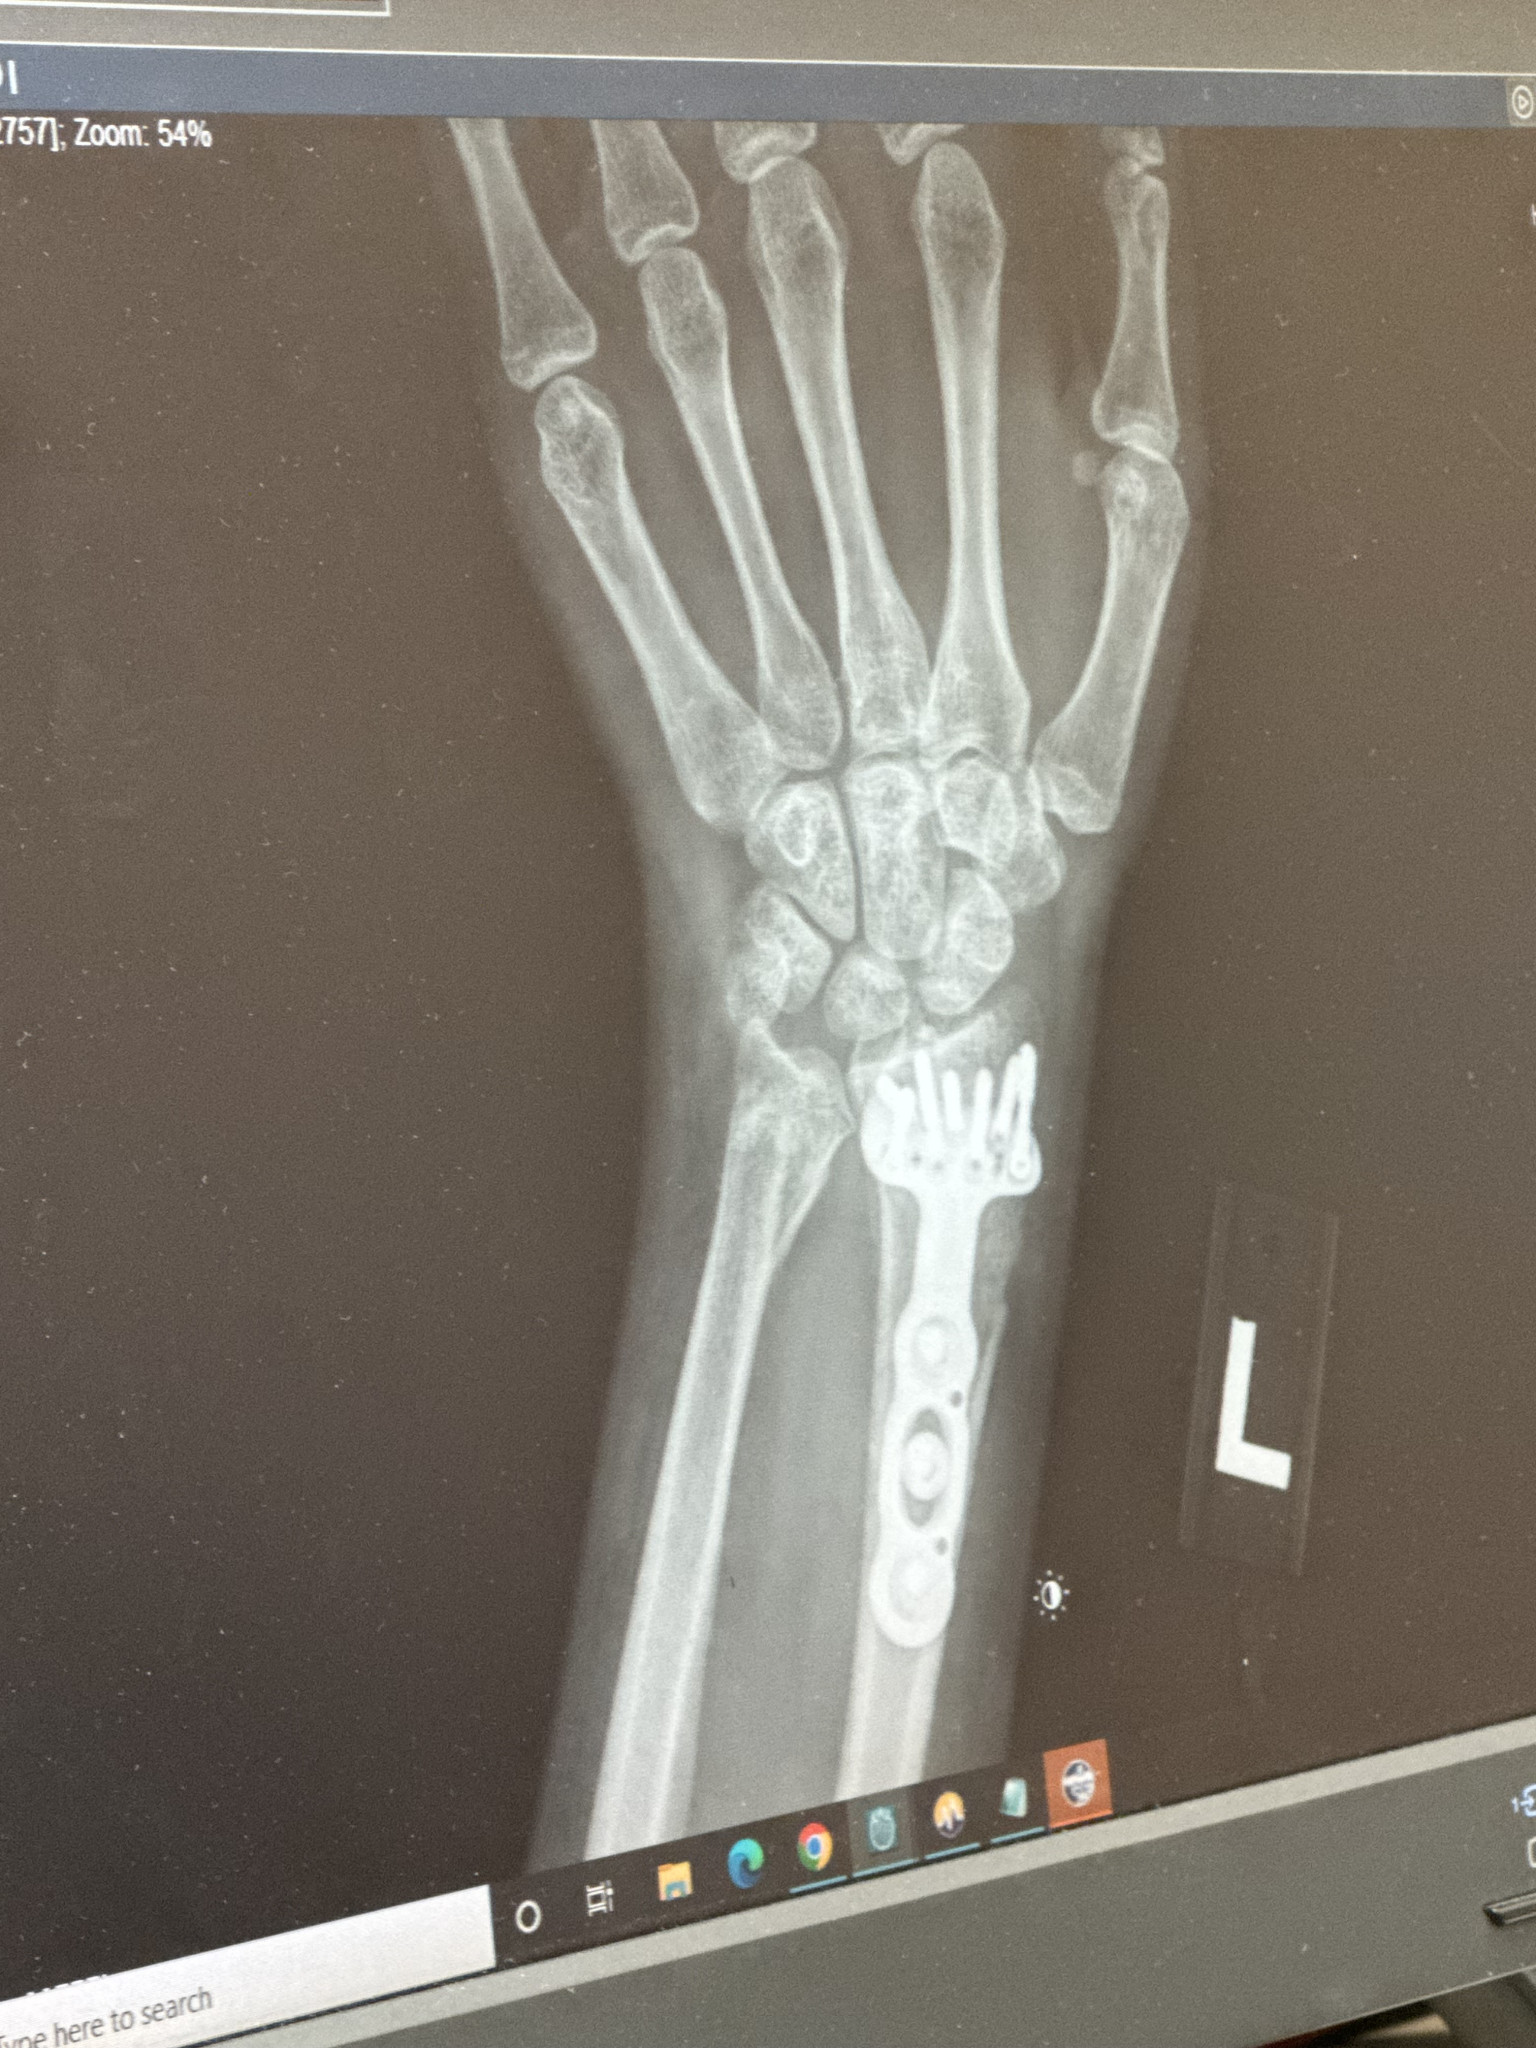

After a car accident, surgery, and months of PT, I still stepped on a bodybuilding stage. My dedication is why I’m the next Ms. Health & Fit